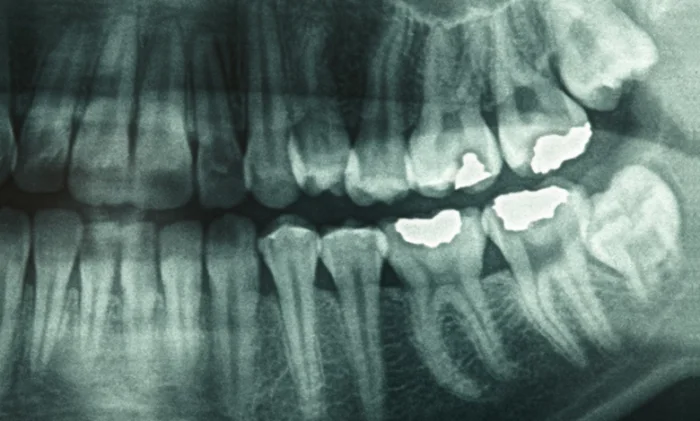

В то время как большая часть зуба не растет, как только он появляется в вашей челюсти, ткани вокруг корней растут. Этот материал, известный как цемент, регулярно добавляет новые слои после поверхностей зубов. И для этого исследования исследователи исследовали гипотезу, что основные физиологические события оставят свой след в этих слоях.

Затем исследователи использовали ряд методов визуализации для изучения колец цемента в корнях зубов и определения возраста, которому соответствуют разные кольца. И, разумеется, кольца разных цветов соответствовали эпохам, когда люди подвергались крупным биологическим событиям.